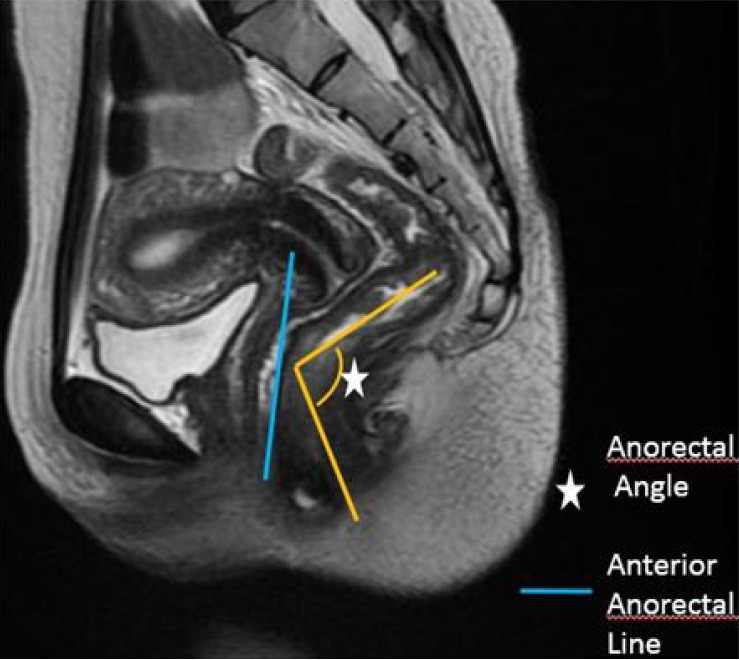

Results: Pelvic floor descent and anorectal junction descent were the most frequent findings, each present in 94.7% of cases. Rectocele was observed in 78.9% of patients, while vaginal or uterine prolapse was seen in 59.4% of females. Less common abnormalities included paradoxical contraction (7%), and there were no cases of sigmoidocele. Functional measurements showed significant differences in pelvic floor dynamics between rest and defecation, particularly in the H-line, M-line, and descent of pelvic organs (P < 0.05).

Conclusion: Pelvic floor descent and anorectal descent were the most common findings in patients suffering from ODS, followed by rectocele. Younger females (< 30 years) were most affected.